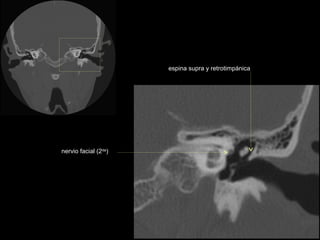

CATEDRA DE RADIOLOGIA U.N.L.P.   Hueso temporal normal        Edición 2002

espina supra y retrotimpánica

nervio facial (2da)

nervio facial (1era)

conducto auditivo interno

cresta falciforme

promontorio

estribo

ventana oval

membrana

timpánica

conducto semicircular

externo

superior

antro mastoideo

ventana redonda

nervio facial (3era)

conducto semicircular externo

conducto semicircular superior